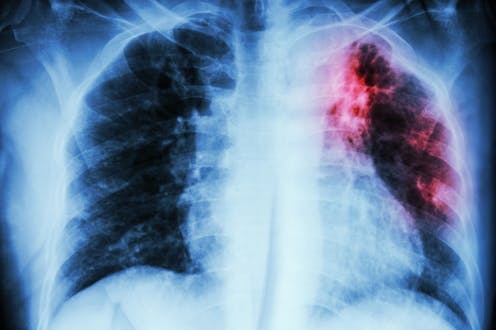

Tuberculosis is the world’s deadliest bacterial infection. It afflicted over 10 million people and took 1.3 million lives in 2022. These numbers are predicted to increase dramatically because of the spread of multidrug-resistant TB.

My team and I wanted to identify what variables can predict how a patient responds to TB treatment. So we analyzed more than 200 types of clinical test results, medical imaging and drug prescriptions from over 5,000 TB patients in 10 countries. We examined demographic information such as age and gender, prior treatment history and whether patients had other conditions. Finally, we also analyzed data on various TB strains, such as what drugs the pathogen is resistant to and what genetic mutations the pathogen had.